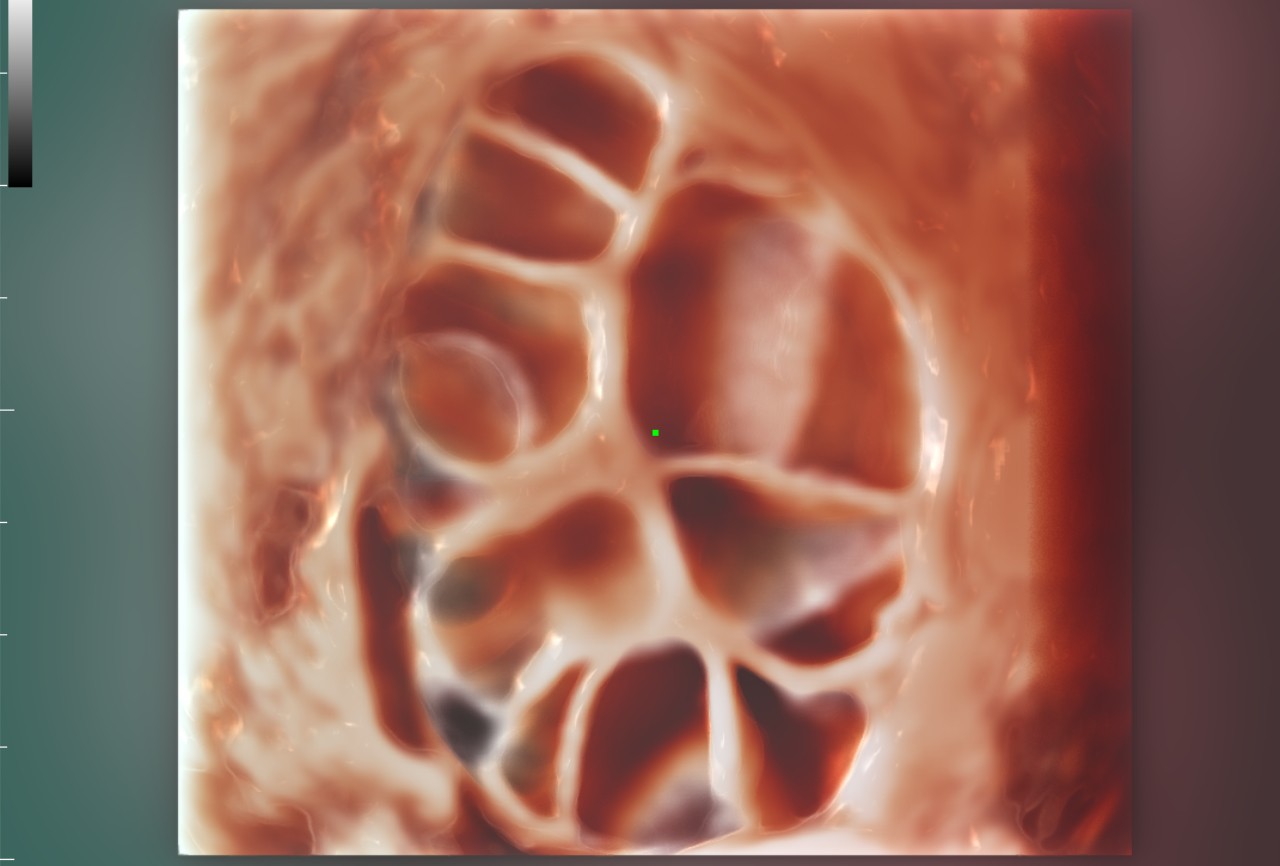

WomenŌĆÖs health is the foundation of health for all and is especially important for countries with aging populations and low fertility levels. MindrayŌĆÖs solution protects multiple life stages, including reproduction, prenatal and intrapartum, and postpartum pelvic floor, with accurate images and efficient and easy-to-use intelligent applications to help caring womenŌĆÖs health in all aspects and cycles.